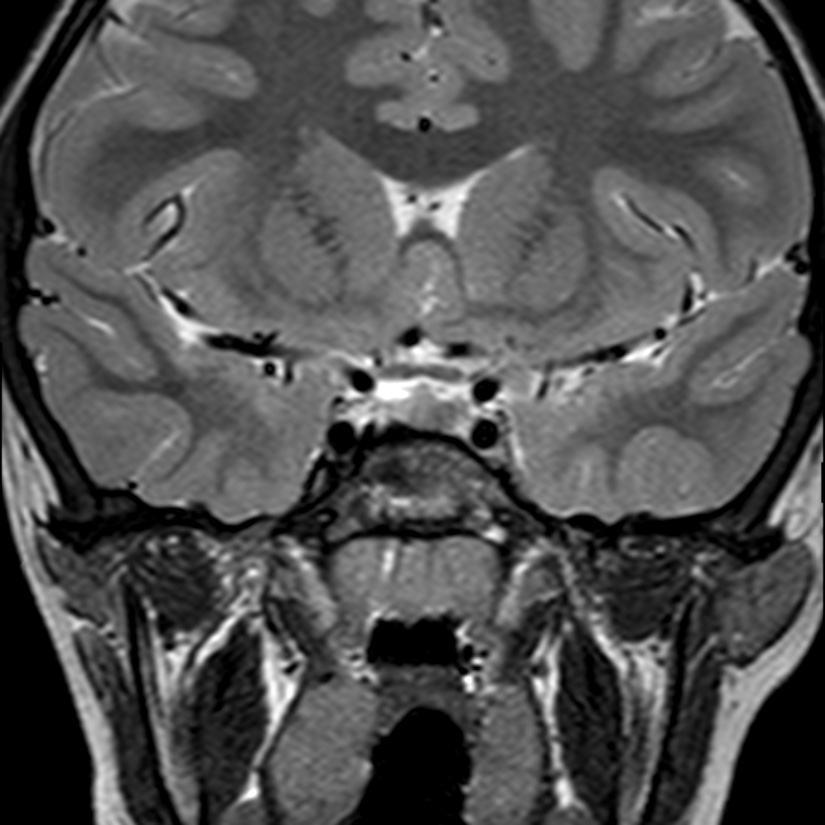

Caso neurorradiología

Paciente de 60 años con cuadro de 1 semana de evolución consistente en tropiezos frecuentes y alteración en la movilidad del miembro

inferior derecho. No refiere

cefalea u otros síntomas asociados, no pérdida de peso, no náuseas o emesis, no

sudoración nocturna. Antecedentes de hipertensión arterial y diabetes.

Resonancia magnética